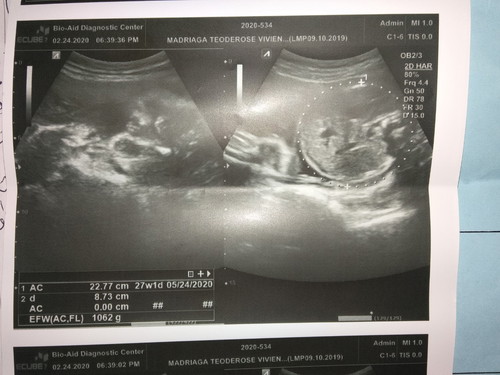

Hi mga mamshiee, baka merong marunong mag interpret sa inyo ng ultrasound picture nasaan po ba ang ulo ni Baby dito hehe. Please respect. Thankyou! ❤️

Yung right side po na may bilog ang ulo or head circumference